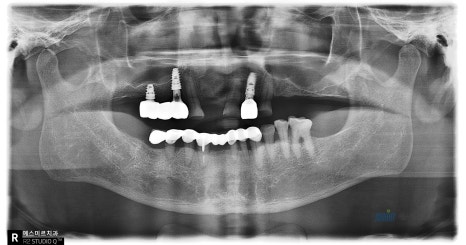

์์ ์ ํ๋ ธ๋ผ๋ง์ ๊ตฌ๊ฐ์ฌ์ง